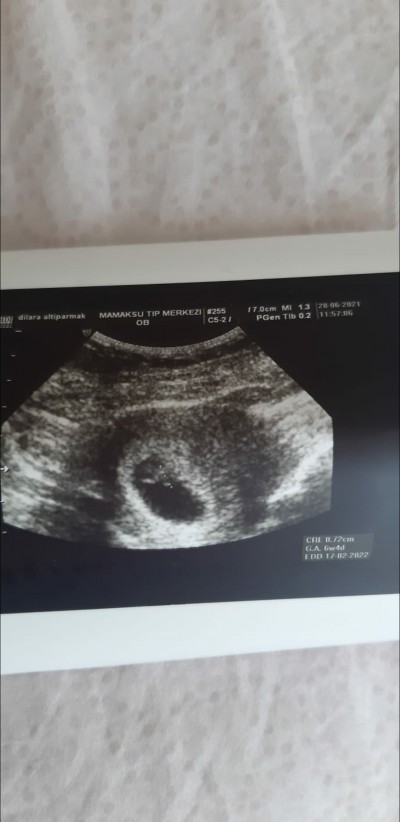

asiri ikize benziyoru 7. haftamda gittigimde benimki boyle gozukmuyordu gerci benimki 4 gun geriden geliyor bak kesin ikizdir :)

image

Aynen hiç bişey gözükmüyor gerçekten